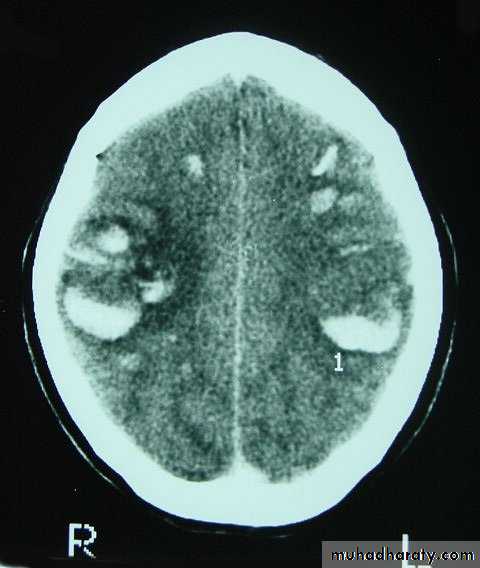

Chronic Subdural Haematoma

Most common in infants and in adults over 60 years of age secondary to SLIGHT blow to the head which may pass unnoticed.

Source of bleeding (haematoma): usually from bridging veins as they pass to the venous sinuses.

The patients present with progressive neurological deficits more than 3 weeks after the trauma.

The initial head injury is often completely forgotten.

CT scan: the acute clotted blood is initially appears white (hyperdence), but as it liquefies, it slowly becomes black (hypodense).

They should be drained if they continue to enlarge.

They are evacuated by drilling burrholes over the collection and washing it out with warmed saline.